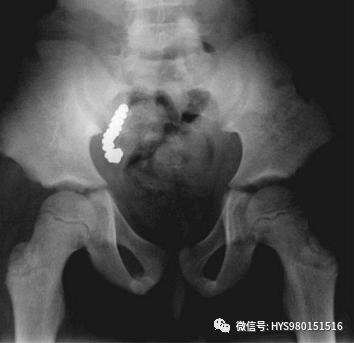

35岁男性因直肠出血和腹痛被送进急诊。

查体发现腹部有异物,但是无外伤。直肠指检发现异物但是无法看到。患者生命体征平稳之后进行X光片检查,情况如上图……

外科手术取出啤酒瓶之后给予抗生素和镇痛药物,患者恢复良好出院。

从肛门塞入异物然后取不出来的其实不少。这个病例发表在2010年的《新英格兰医学杂志》上。